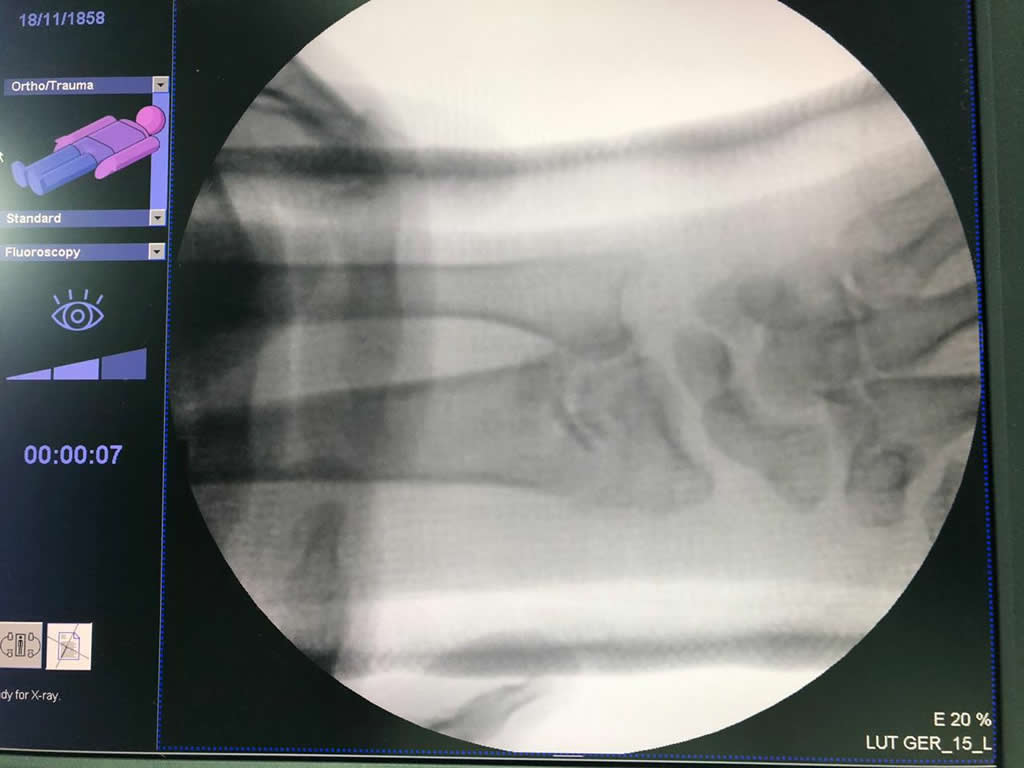

Calcaneo - Cirugías de Muñecas y Manos

Los procedimientos más comunes en cirugía de la mano son aquellos destinados a reparar traumatismos, incluyendo lesiones de tendones, nervios, vasos sanguíneos, y articulaciones; huesos fracturados; y quemaduras, cortes, y otros daños de la piel.